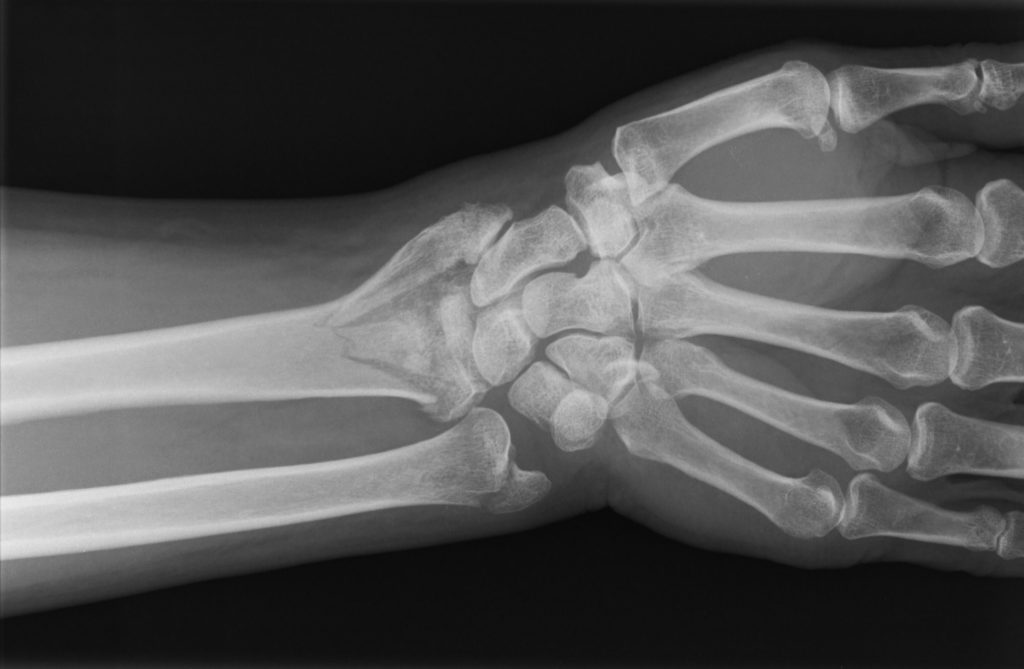

La muñeca está formada por ocho pequeños huesos que se conectan con los dos huesos largos del antebrazo, llamados radio y cúbito. Aunque las fracturas de la muñeca pueden afectar a cualquiera de estos diez huesos, el hueso que se rompe más frecuentemente es, con diferencia, el radio. Esta situación se conoce entre los Cirujanos de la Mano con el nombre de “fractura distal del radio” o «fractura de extremidad distal del radio» (Figura 1).

PATOLOGIAS MUÑECA - FRACTURAS DE LA MUÑECA Figura 1 - Fractura de muñeca o fractura de extremidad distal del radio.

Figura 1 - Fractura de muñeca o fractura de extremidad distal del radio.